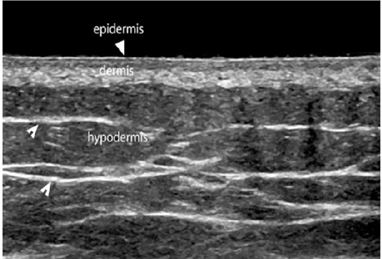

Ultrasound imaging of superficial tissues allows for the visualization of :

• Epidermis, the outermost layer, which appears as a thin, uniform hyperechoic line.

• Dermis, located deeper, which appears as a hyperechoic band (although less hyperechoic than the epidermis), with thickness varying according to the anatomical region. The dermis comprises a more superficial papillary dermis, which is more hypoechoic due to its high water content, and a deeper reticular dermis, which is more hyperechoic because of the density and orientation of collagen fibers. The epidermis, papillary dermis, and reticular dermis together form the dermo-epidermal complex (DEC).

• Hypodermis/subcutis (SUBC), the innermost layer, clearly separated from the DEC by the dermo- hypodermal junction, a continuous, well-defined line reflecting the structural differences between the dermis and hypodermis. The hypodermis appears hypoechoic, organized into lobules, and intersected by thin horizontal or oblique hyperechoic lines representing connective-tissue septa (scaffolds) through which lymphatic vessels run. These septa tend to be parallel to the muscular fascia and may form interconnections with it. The end of this layer is marked by the beginning of the muscular layer, and its thickness varies according to anatomical site and adipose-tissue content.

A proper evaluation of superficial tissues should also include the generous application of gel and the use of minimal pressure during probe manipulation. These precautions help prevent excessive deformation of the underlying tissues, allowing for an accurate visualization of structures without operator-induced artifacts [Figure 4].

Figure 4 Ultrasound of superficial tissues in a healthy subject. The hyperechoic epidermis, the hypoechoic papillary dermis, and the hyperechoic reticular dermis can be identified, as well as the hypoechoic hypodermis traversed by hyperechoic fibrous septa.